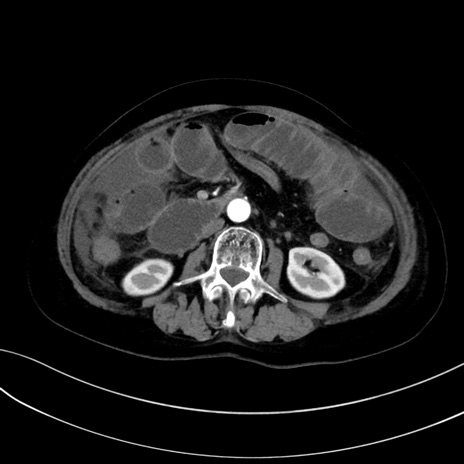

症例13 CT(横断像)1日半後